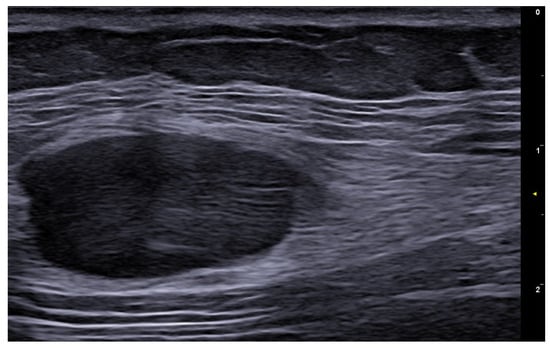

- Iannone, M.; Janowska, A.; Oranges, T.; Balderi, L.; Benincasa, B.B.; Vitali, S.; Tonini, G.; Morganti, R.; Romanelli, M.; Dini, V. Ultrasound-guided injection of intralesional steroids in acute hidradenitis suppurativa lesions: A prospective study. Dermatol. Ther. 2021, 34, e15068. [Google Scholar] [CrossRef] [PubMed]